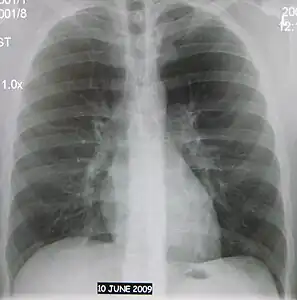

- Normal AP CXR

The discovery of x-rays made it possible to determine the anatomic type of pneumonia without direct examination of the lungs at autopsy and led to the development of a radiological classification. Early investigators distinguished between typical lobar pneumonia and atypical (e.g. Chlamydophila) or viral pneumonia using the location, distribution, and appearance of the opacities they saw on chest x-rays. Certain x-ray findings can be used to help predict the course of illness, although it is not possible to clearly determine the microbiologic cause of a pneumonia with x-rays alone.